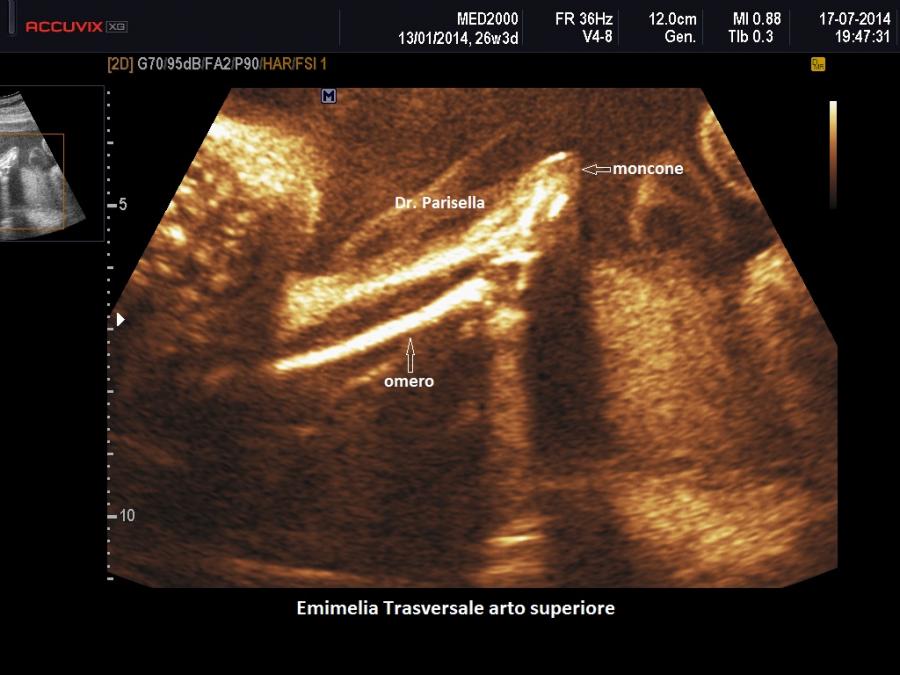

L'Emimelia è un difetto che interessa i segmenti mesomelico e acromelico. Può essere classificata in due tipi: 1) longitudinale quando a mancare è il raggio osseo mediale o laterale di un arto, cioè manca uno tra radio e ulna o uno tra tibia e perone; di solito radio e perone sono i più colpiti; nell'emimelia radiale si associa una mano torta; 2) trasversale quando manca completamente la parte distale di un arto: in questi casi in genere è presente un moncone tipo amputazione.